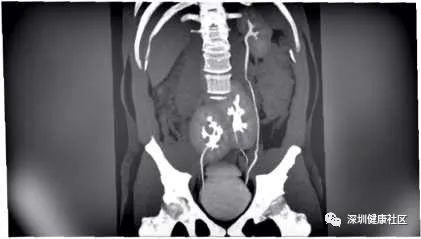

前几天刚刚(2020年5月6日)在《新英格兰医学杂志》(NEJM)上发表的一份病例报告,并有图片可见,让人确信真有这回事。

巴西有一名男子因腰部疼痛去医院就诊。圣保罗的Do Rim医院的医生们,为了找到腰痛的原因,行腰部 CT扫描。腰部扫描不仅仅看到了腰椎,腹部器官也可以看到。扫描结果显示,其椎间盘突出或“滑落”,就是腰椎之间的垫状椎间盘部分移位了。阅片时医生发现奇怪的东西在腹部:有三个类似肾脏的器官。随即做了尿液、血液检查,做了肾脏造影。最后确实是肾脏,有三个,而不是两个,都有功能的(即是排尿功能)。左边的肾脏看起来很正常,与其他绝大多数的人的位置一样,也是通过左输尿管与膀胱直接相连。而右边靠近骨盆的地方有两个融合的肾脏,有两条输尿管与膀胱相连。NEJM报告的作者说,患者没有尿频、尿急、夜尿多等症状,平时未有腰痛腰酸等不适症状。查肾功能、尿蛋白都正常。作者说,由于这种情况通常不会引起症状,人们也不知道自己是这种情况,除非是通过不相关的医学测试或体检意外发现的。这名男子的多余肾脏也不需要任何治疗和特别的护理。但报道称,由于椎间盘突出使背部疼痛,医生开具了止痛药进行治疗。

搜索中国知网、万方、pubmed。2013年发表在Internet Journal of Radiology上的一篇类似病例的报告显示,拥有三个肾脏的情况很少见,医学文献中报告的病例不到100例。这种情况被认为是在胚胎发育期间出现的,当时有一个肾脏的结构一分为二了。